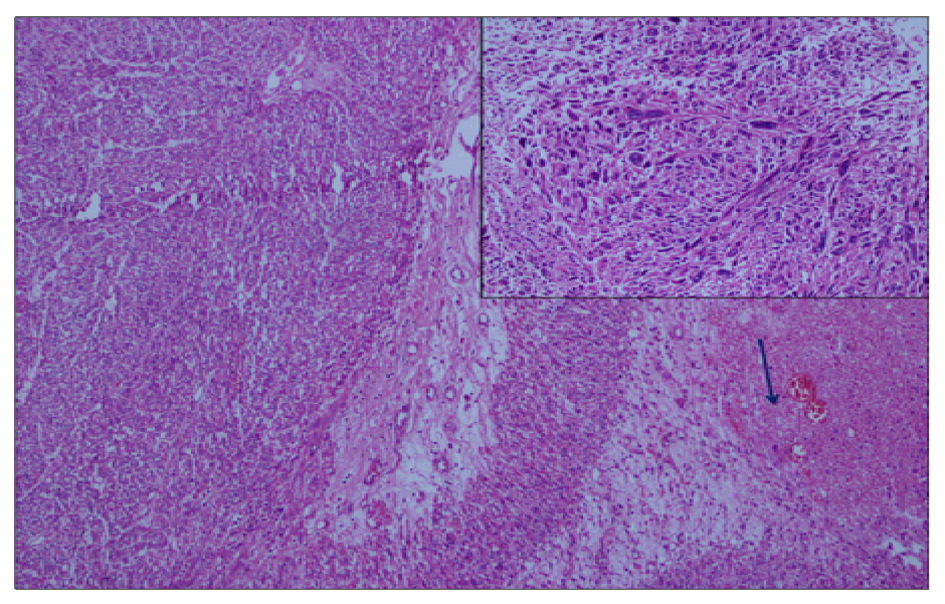

Pathological examination revealed primary high-grade renal leiomyosarcoma. Macroscopic findings were as follows: A tumor with the biggest diameter of 8 cm was seen on the renal hilus which was pinky-yellow in color, well-circumscribed and showing hemorrhages and cystic features in a focal area (Fig. 3). Microscopic examination reported that pleomorphism (small picture) and necrosis (blue arrow) were remarkable in the tumor consisting of the cells with pink cytoplasm and spindle nucleus crossing with each other from several angles. Rates of necrosis and mitosis were 16-20/10HPF (Fig. 4) (H&E, × 100, 200). In the immunohistochemical examination DKA was positive, desmin (+), CD117 (-), CD34 (-) and S-100 was (-) (Fig. 5, 6). Ki-67 proliferation index was found to be 15%. No distant metastases were found on the PET/CT. The patient was placed in follow-up program.

![]() Click for large image | Figure 4. Hematoxilyn-eosin staining demonstrating high-grade sarcomatoid cells. H&E (× 100, 200). Pleomorfism (small figure) and necrosis (arrow). |